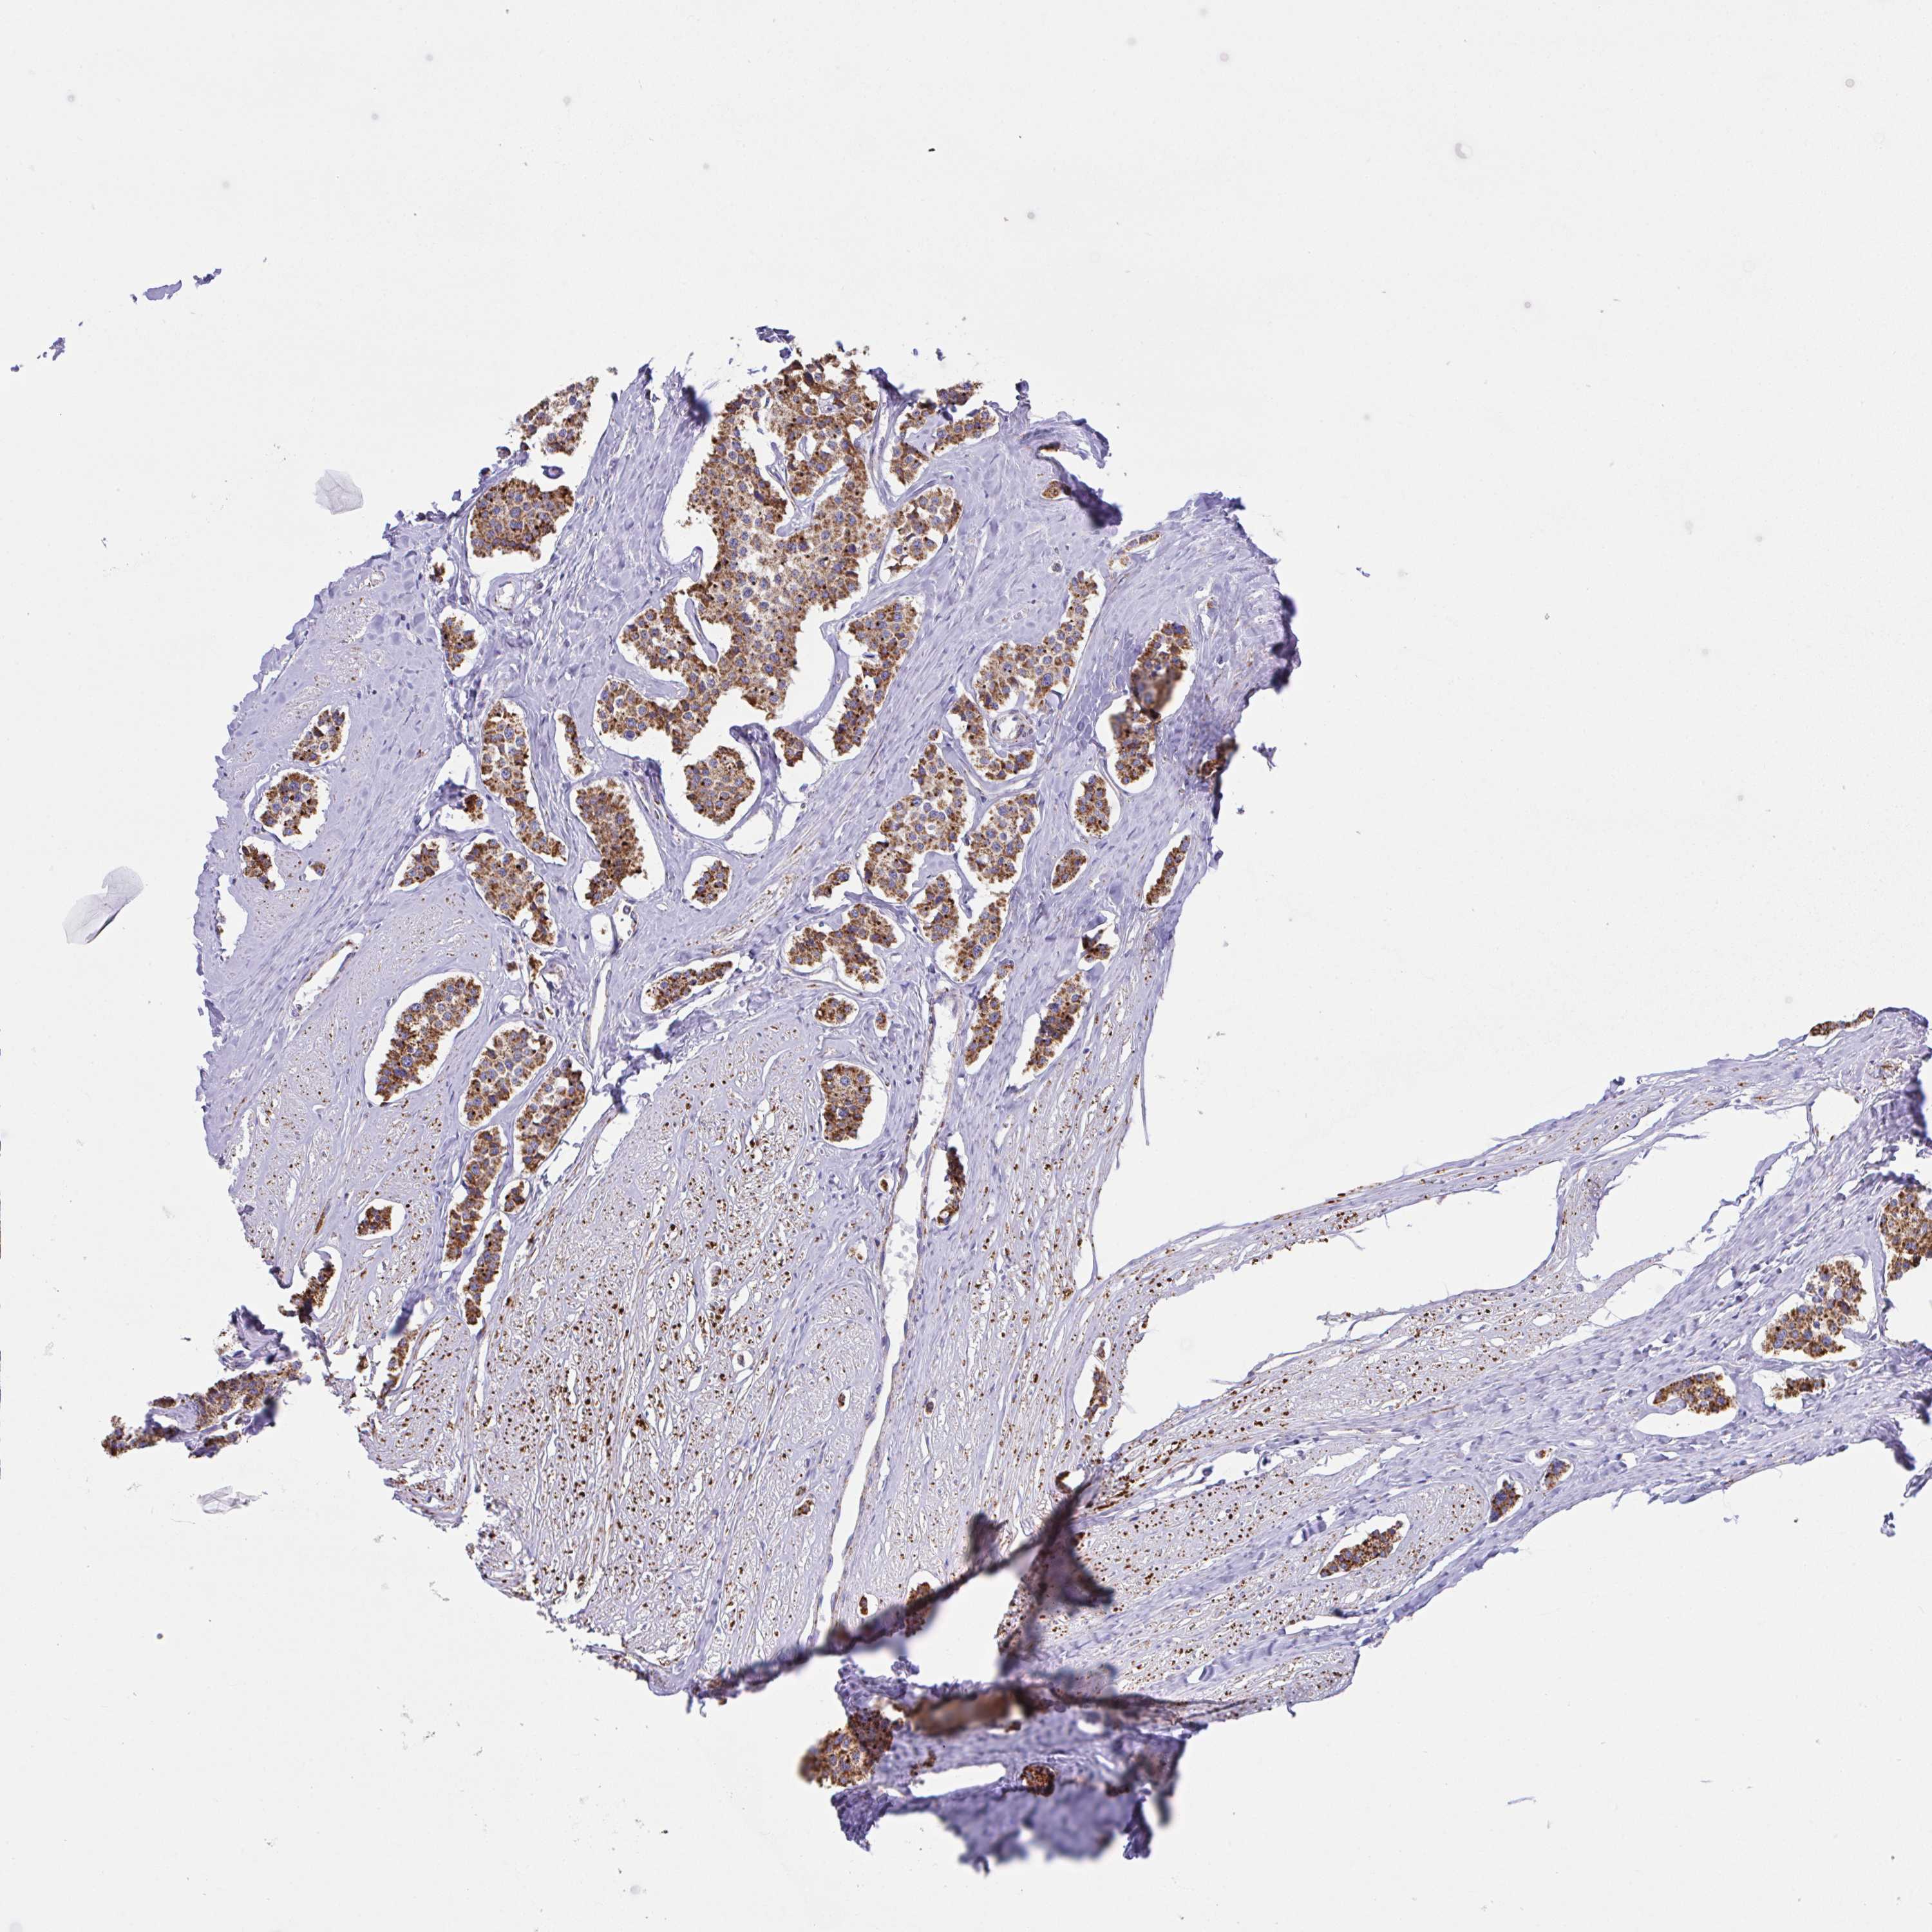

CARCINOID - Protein expressioni

A mouse-over function shows sample information and annotation data. Click on an image to view it in a full screen mode. Samples can be filtered based on level of antibody staining by selecting one or several of the following categories: high, medium, low and not detected. The assay and annotation is described here.

Antibody stainingi

Antibody staining in the annotated cell types in the current human tissue is reported as not detected, low, medium, or high, based on conventional immunohistochemistry profiling in selected tissues. This score is based on the combination of the staining intensity and fraction of stained cells.

Each image is clickable and will lead to virtual microscopy that enables deeper exploration of all samples and also displays staining intensity scores, fraction scores and subcellular localization as well as patient and tissue information for each sample.

Antibody HPA057849

Staining

High

Intensity

Strong

Quantity

>75%

Location

Nuclear

Carcinoid, malignant, NOS